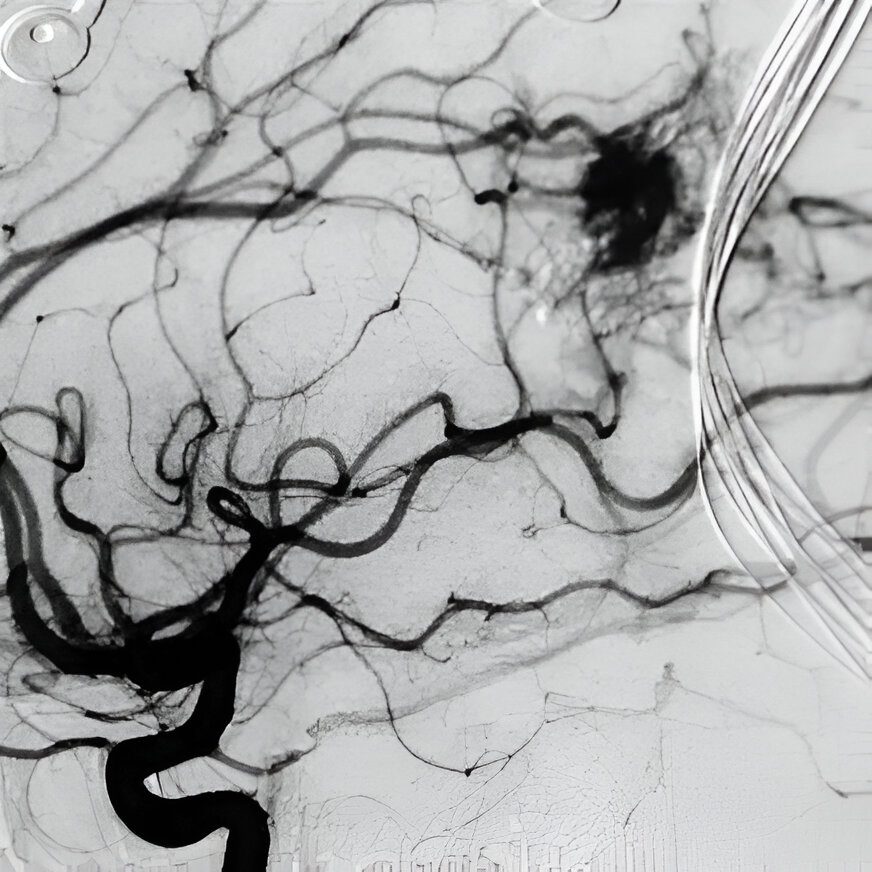

Angiogram of my AVM (Arterial Venus Malformation). With the kind of hemorrhage I had and for the length of my bleed, I should be dead… I know now God spared my life, because I would not have been ready.